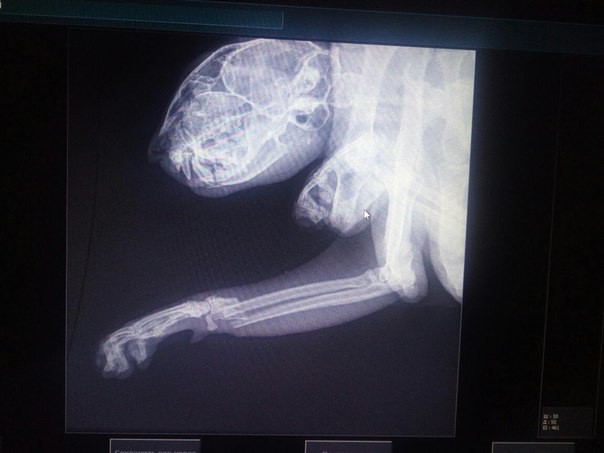

Друзья, позвонила бабушка пенсионерка, которая нашла лежащего без движения котика. В ветеринарке определили, что у него перелом передних лапок и травмирована челюсть. Ветврач сказал, что по характеру повреждений котейка, скорее всего, выпал из окна. Еще одна версия, что попал под машину. Котик похож на домашнего. Сейчас лежит в коробке по адресу ул. Чебрикова 34.

Развесили объявления в надежде найти хозяев. В противном случае как-то сообща надо спасать бедолагу. На данный момент ему сделаны обезболивающие уколы.

Конечно, для остеосинтеза и «сборки» челюсти средства немалые нужны…

Вторую лапу не диагностировали(((

С челюстью вообще большая проблема — перелом 2-х дужек нижней челюсти. Даже для опытного хирурга это сложная задача, но Д.Ф. не отказался, сейчас идёт операция. Стоимость операции хирург оценил в 15 тыс… кто бы знал. Две лапы, челюсть, хоть бы наркоз выдержал Бельчик.

Раз Д.Ф. взялся, значит надежда есть, хотя у него тоже бывают «потери». Завтра котик отойдёт от наркоза, видно будет. Если челюсть зафиксирована, думаю капельницу поставят для поддержки организма. Он до операции уже был обезвожен (((